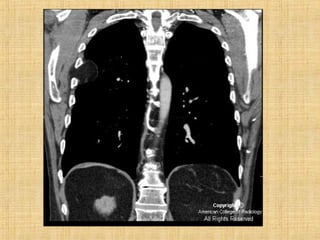

As principais informações do documento são: 1. Discute os padrões de doença pulmonar causados por metástases, incluindo nódulos, espessamento intersticial e obstrução das vias aéreas. 2. A prevalência de metástases pulmonares varia de 30-55% dependendo do tumor primário, e são mais comuns em pacientes acima de 50 anos. 3. Os achados clínicos mais comuns são dispneia, hemoptise e febre, enquanto exames de escarro ou lavado brô